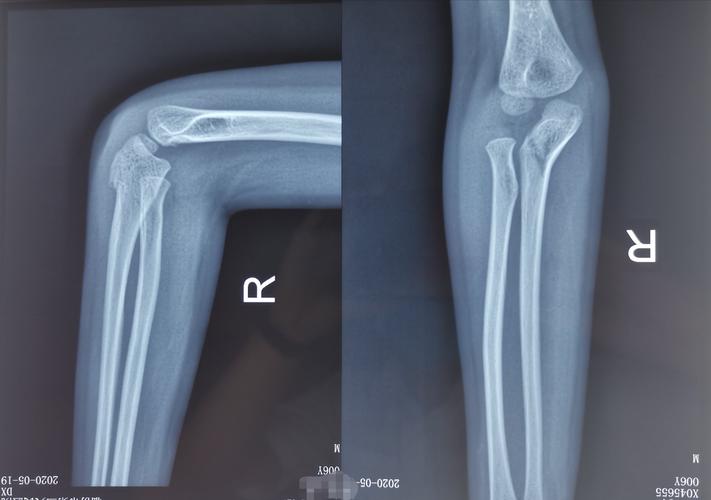

儿童孟氏骨折

儿童骨折的陷阱:儿童孟氏骨折脱位

小儿孟氏骨折图片